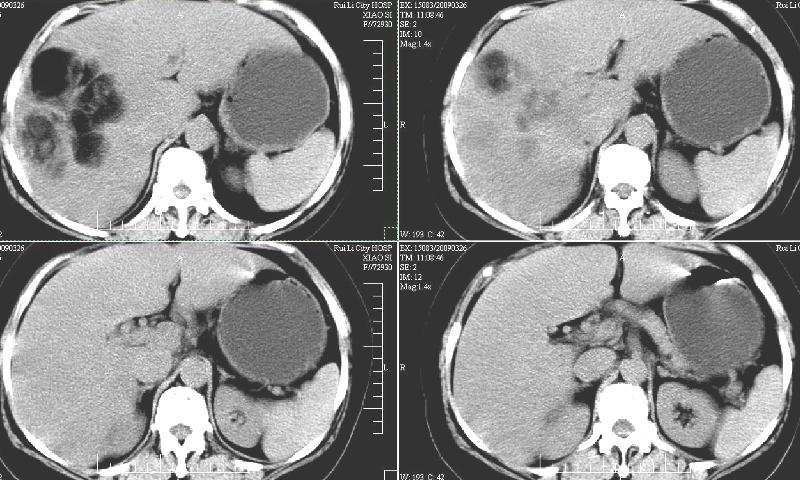

标题: CT19130:F,60岁。2008-10-17CT发现肝脏占位,现在复查! [打印本页]

标题: CT19130:F,60岁。2008-10-17CT发现肝脏占位,现在复查!

前次已经增强,所以这次没有增。ct:肝右叶平滑肌血管脂肪瘤治疗后复查,肿瘤大小同前或略有缩小。2、轻度脂肪肝。3、肝左叶小囊肿

支持楼主意见,肝右叶平滑肌血管脂肪瘤。